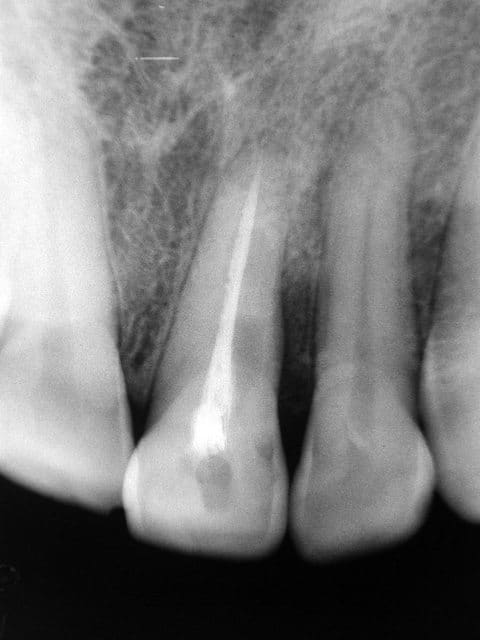

L'an dernier guttaman nous faisait découvrir une radio bonne à vous donner des cauchemars et signée Dr Sleiman ( un autre as de l'endo ?)

http://www.eugenol.com/eugenol/file.php?8,file=1128 : tout à la force du poignet pourrait-on dire.

J'avoue que j'y pense souvent quand je me lance dans une bio sur une centrale ; quant à l'égaler, c'est une autre histoire.